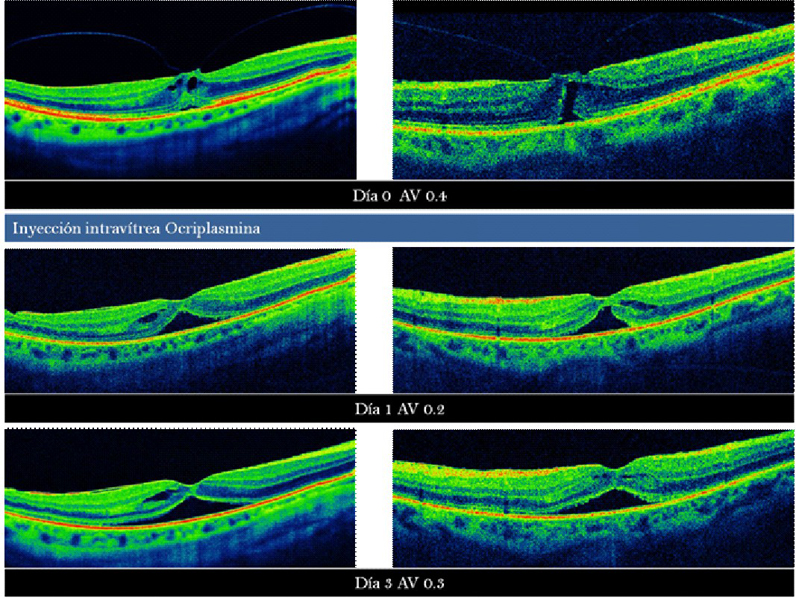

Cierre por vitreólisis enzimática

Recientemente ha salido al mercado la ocriplasmina, el primer fármaco capaz de realizar una vitreólisis enzimática. Está indicada en pacientes con tracciones vitreomaculares sintomáticas y agujeros maculares con tracción vitreomacular asociada

7 (

Figura 12). Los pacientes que parecen beneficiarse más de este fármaco son los jóvenes, fáquicos y sin membrana epiretiniana

19.

Figura 12. Tracción vitreomacular con agujero macular (incompleto). Se realizó tratamiento con vitreólisis enzimática (ocriplasmina).